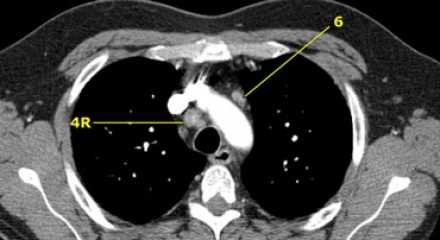

На изображении слева 3А узел в преваскулярном пространстве. Обратите внимание так же на ниже расположенные паратрахеальные узлы справа относящиеся к 4R группе.

4R. Правые нижние паратрахеальные лимфатические узлы

- Верхняя граница: пересечение нижнего края левой плечеголовной вены с трахеей.

- Нижняя граница: нижний края непарной вены. 4R узлы распространяются до левого края трахеи.

На изображении слева мы видим 4R паратрахеальные узлы. Кроме того здесь представлен узел кнаружи от дуги аорты, то есть 6 группы.